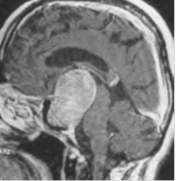

VII. CIRUGIA DE HIPOFISIS

Se complementerá y trabajará en conjunto con la clinica de hipofisis de endoncrinologia haciendo una discusion de los casos apoyandose en los consultores

con los que cuenta el grupo. Tomando la mejor decisión y mas adecuada conducta para cada paciente. Cirugia endoscopica transnasal y transcraneana microscópica

para patologia de hipofisis (NO Pos se debe crear tarifa institucional).